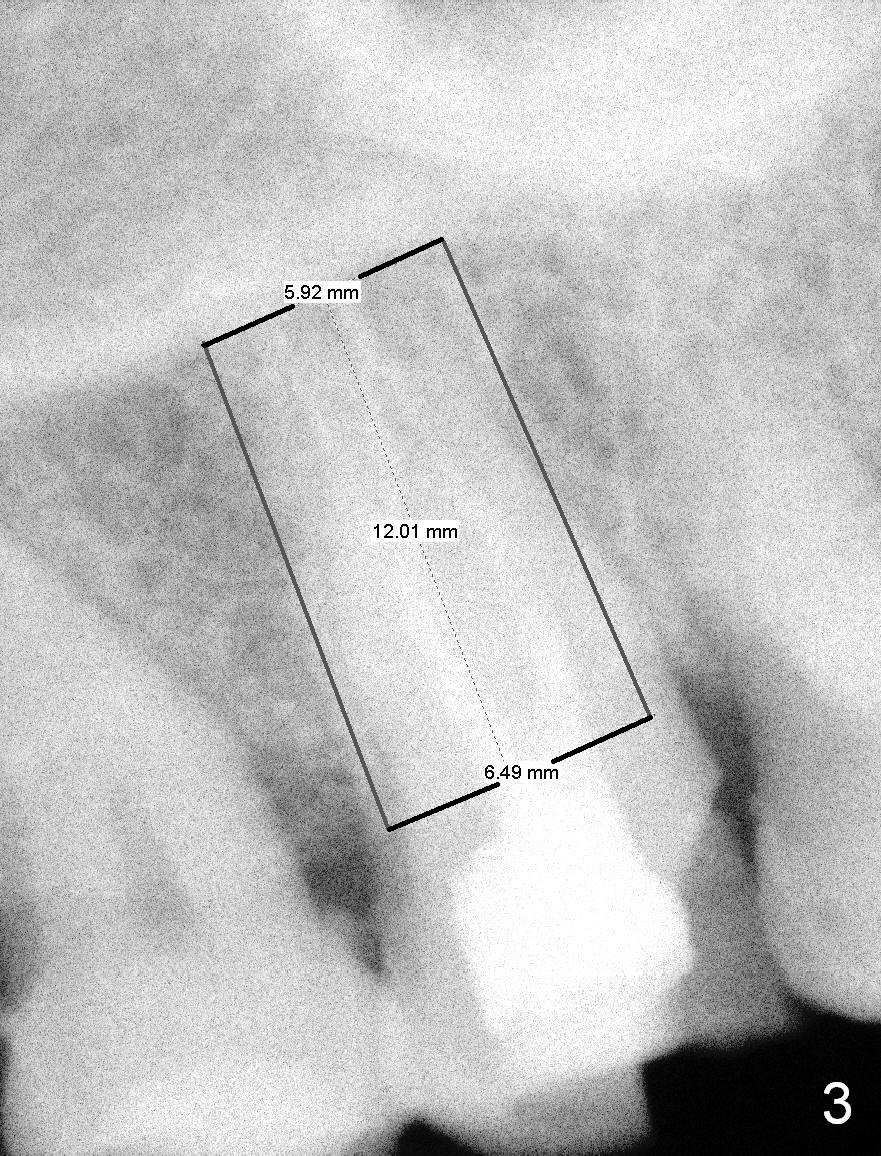

A 65-year-old lady is at early stage of Parkinson's disease and appears to be a bruxer. There are multiple chipped teeth, including #2 (Fig.1,4 *). She chooses implant over RCT retreat. A tissue-level implant (Fig.2) matches the root shape of the affected tooth better than a bone-level one (Fig.3), because of taper. The buccopalatal and mesiodistal dimensions of the extraction socket are 11 and 8 mm, respectively (Fig.5,7).

Osteotomy for immediate implant is initiated with a 2 mm pilot drill (Fig.6b red arrow) in the coronal end of the buccal slope of the septum (center of the socket). Once the drill gets initial penetration, the trajectory changes to the long axis of the tooth (Fig.6c). Then PA is taken with a parallel pin (Fig.7). It appears that the depth is not enough; there is bone apical to the pin. As osteotomy increases in diameter, burs may be deviated buccally due to the septal buccal slope (to be discussed below). With longer osteotomy, the deviation may be less. Osteotomy is deepened (Fig.6d). From this moment on, nose blowing test is done after each step. The result is all negative. As drill diameter increases, they do deviate buccally (Fig.6e arrow), since there is less bone contact buccally than lingually (compare Fig.6e,f). With the same reason, smaller tapered taps (Fig.6g pink, 5 and 6 mm) tend to be mobile buccally (arrow). When a large tap (7 mm) is inserted (Fig.8), there is no buccal mobility. It appears that the tap contacts more of the buccal plate (Fig.6h), but the coronal end of the tap is buccal (Fig.6i, pink circle). At each step of osteotomy, the coronal end of a bur or tap should be pushed as lingual as possible so that the final tap is favorable for restoration (Fig.6j). Sinus lift is done (Fig.6k red circle; Fig.9 *) before placement of 7x17 mm implant (I, >60 Ncm). Since the palatal socket is not associated with implant stability, it is closed by collagen plug (Fig.6l, blue area). As extra precaution, bone graft is placed around the coronal portion of the tissue-level implant (Fig.6l red circles), followed by collagen dressing.